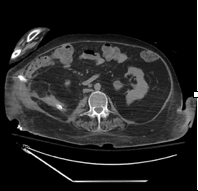

Case Presentation: A 56-year-old female with history of spastic quadriplegia secondary to multiple sclerosis, neurogenic bladder with a long-term indwelling suprapubic catheter presented with septic shock. Labs revealed leukocytosis and lactic acidosis. A contrast enhanced computed tomography of abdomen and pelvis revealed a multiloculated large right renal abscess with staghorn calculus extending into the right retroperitoneum consistent with a diagnosis of xanthogranulomatous pyelonephritis. The renal abscess was initially treated with ceftriaxone, metronidazole and percutaneous drainage. Her cultures from the abscess grew Proteus mirabilis. Patient did not show any improvement in the follow up imaging and required laparotomies with staged debridements. Three surgeries were needed culminating in a right sided nephrectomy. Her operative cultures grew Proteus mirabilis, Pseudomonas and Achromobacter. The patient was treated with meropenem and followed till improvement of her abscess.

Discussion: Xanthogranulomatous pyelonephritis (XGP) is a rare and severe form of kidney inflammation characterized by the accumulation of lipid laden macrophages (xanthoma cells) and granulomatous tissue in the kidney. It typically results from chronic urinary tract obstruction, often due to staghorn calculi. Urine cultures usually yield Escherichia coli and Proteus mirabilis. However, Pseudomonas and Klebsiella have also been cultured.Complications can frequently occur in the form of psoas abscess, nephrocutaneous fistulas, nephrocolonic fistulas and paranephric abscesses. Computed tomography remains the mainstay for diagnosing XGP. However, the definitive diagnosis can only be suggested pathologically with findings of the characteristic xanthoma cells. Treatment includes antibiotic therapy and total nephrectomy – although nephron sparing surgery such as partial nephrectomy can sometimes be attempted. Our patient’s primary risk factors included quadriplegia with neurogenic bladder necessitating the use a chronic suprapubic catheter. Xanthogranulomatous pyelonephritis was diagnosed through a CT abdomen and had already evolved to a retroperitoneal abscess. Antibiotic treatment and multiple drains were placed with hopes to decrease the size of the abscess, but this did not resolve her complicated infection and led to further colonization with multi drug resistant organisms. Ultimately the patient had to undergo right sided nephrectomy.